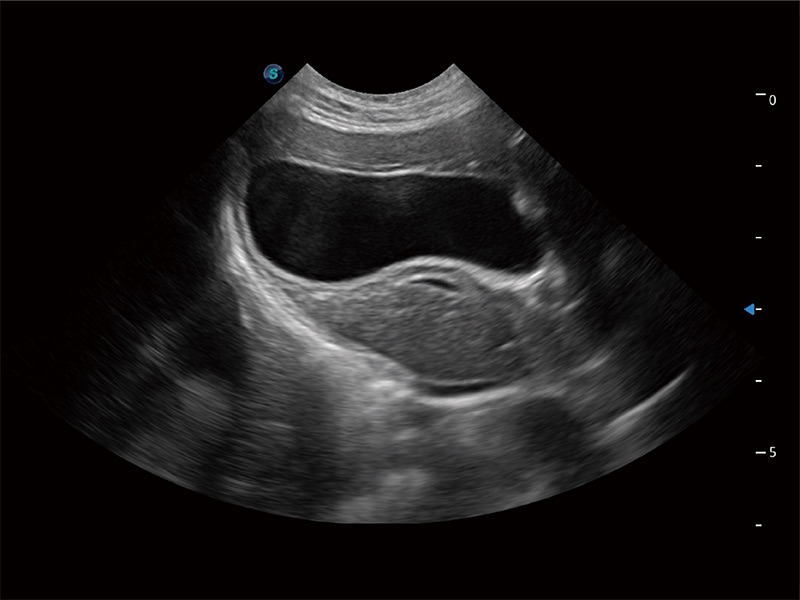

极大提升超低速微细血流的检出能力,同时更精准地滤除软组织和超声信号,为兽用医生提供以往无法通过常规血流获得的疾病诊断信息。

在传统二维血流成像的基础上,呈现血流的立体感,具有动感的生命力之美。即便是微小的血管也能轻松应对,提高了血流的视觉敏感性。